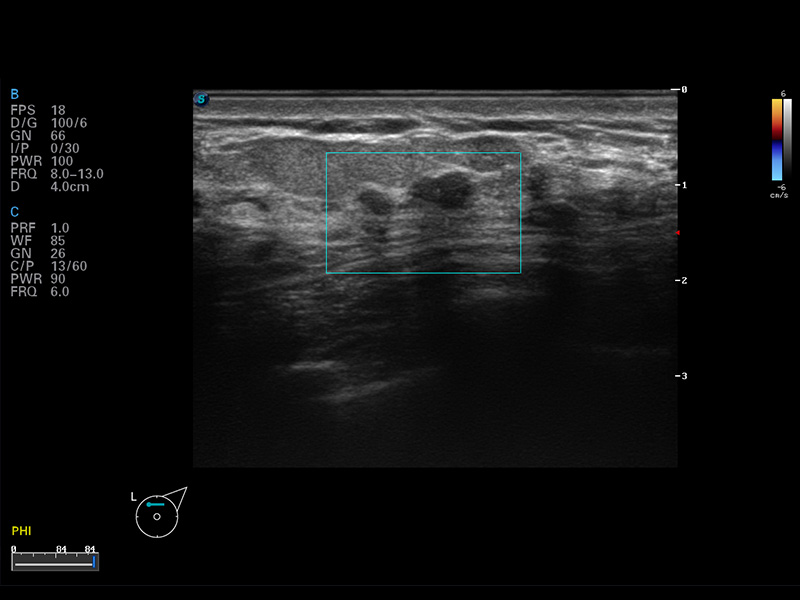

便携式彩色多普勒超声诊断仪

S8 EXP便携式彩色多普勒超声诊断仪是玖鼎集团研发的高端全身应用型便携彩超。高通道的VIS平台融合可视化(Visual)、智能化(Intelligent)和人性化(Smart)的特点,配以玖鼎集团自主研发生产的探头大家族,使您能够快速、准确的获得病人信息,提高工作效率的同时减轻疲劳。

μ-Scan微米成像